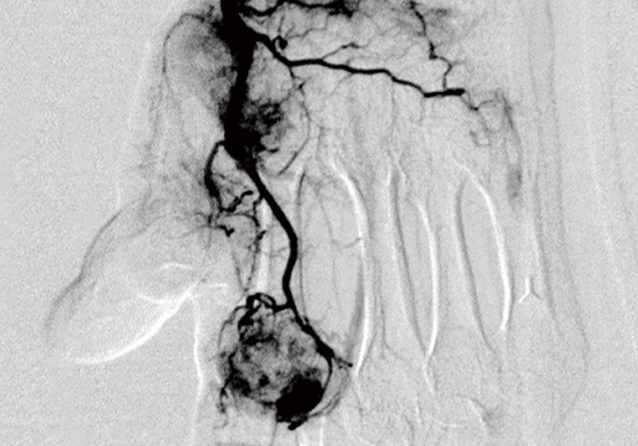

モヤモヤ血管の発生

治りきらない状態が続くと、炎症部位に「モヤモヤ血管」と呼ばれる異常な血管が発生します。これが慢性的な痛みの原因になります。

神経の過敏化

モヤモヤ血管の周囲には痛みを感じる神経が増え、わずかな刺激でも痛みを感じやすい状態になります。